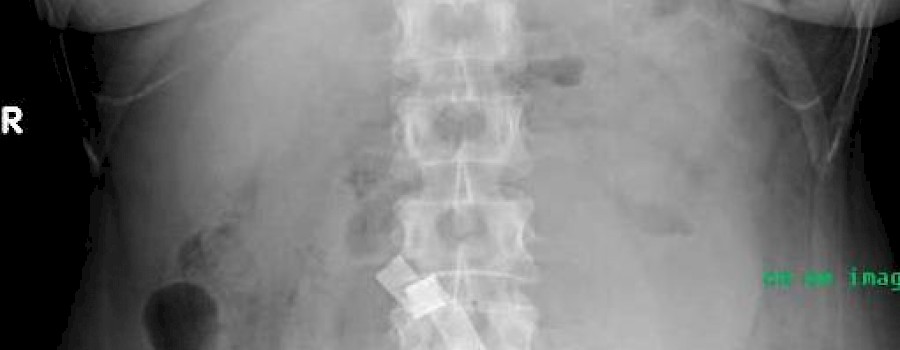

Fremdkörper aus Baumwolle

Gossypibom

Als Gossypibom wird in medizinischen Fachkreisen ein zurückgelassener Frempkörper aus Baumwolle nach chirurgischen Eingriffen bezeichnet. Der Ausdruck Gossypibom setzt sich zusammen aus „gossypium“ (lateinisch: Baumwolle) und „boma“ (Swahili: Versteck).